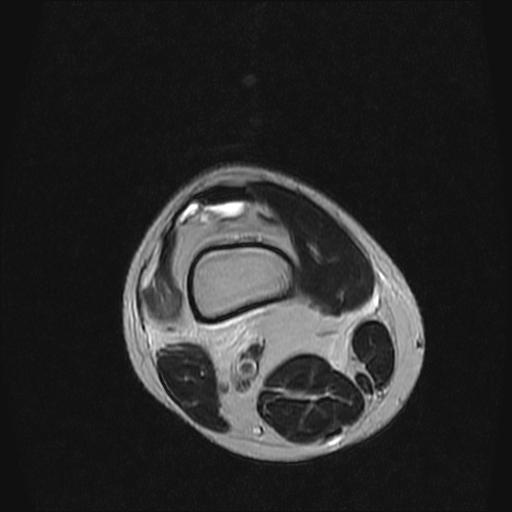

40岁男性,右膝关节外伤,x光平片示,髁间隆突撕脱骨折。

半月板1-2级损伤   前交叉韧带撕裂伤   关节腔少量积液  诸骨未见新鲜外伤性改变

半月板1-2级损伤   前交叉韧带撕裂伤   关节腔少量积液

除了关节积液外并无韧带撕裂,acl胫侧附着点有2束,正常情况下脂肪信号。此病例应加做压脂像以便观察是否有骨损伤。